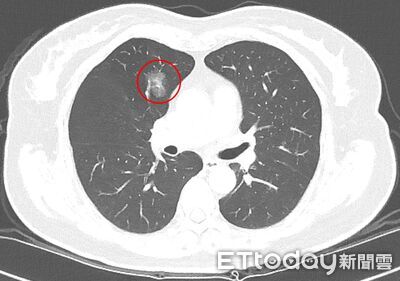

肺癌低劑量電腦斷層(LDCT)篩檢愈來愈普及,某些人覺得太早期發現個案,對患者恐造成困擾,但台北慈濟醫院最新研究顯示,其實肺部結節若進入手術、切片確認的階段,最後結果高達2/3為惡性,且早期肺癌生長速度緩慢,1年僅約增加0.1公分,這凸顯影像判讀、處置決策都不容易,民眾也不能掉以輕心。 《詳全文...》